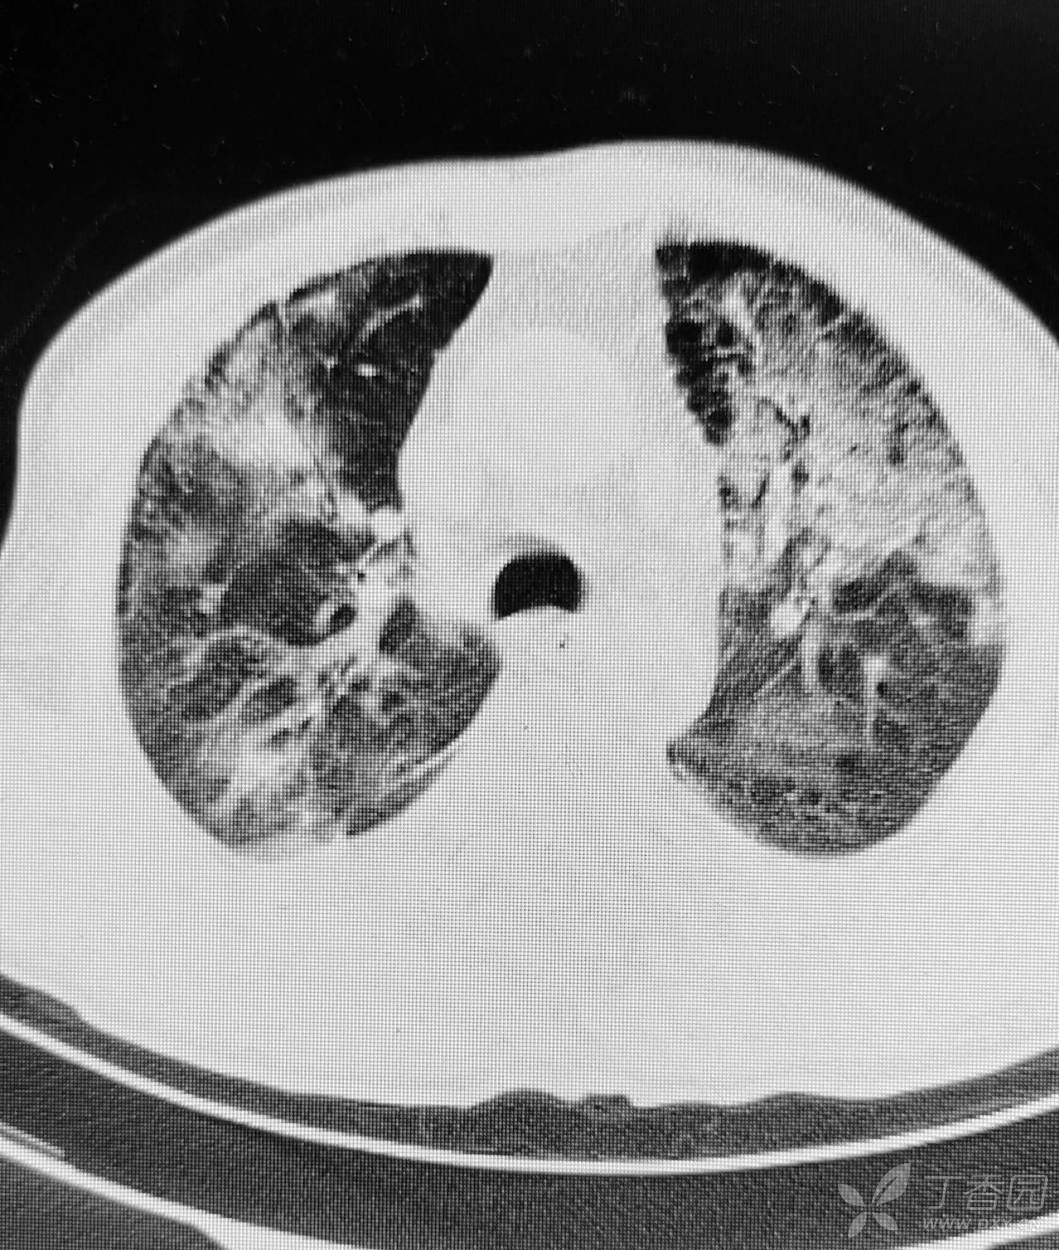

直肠癌术后两个月,接受放化疗一个月。白细胞危急值。

停化疗放疗,升白药物。白细胞增高了。

血小板仍低,血红蛋白开始降低。

胸部影像如图。

目前有血培养阳性,病原菌难以命中。痰培养阳性。